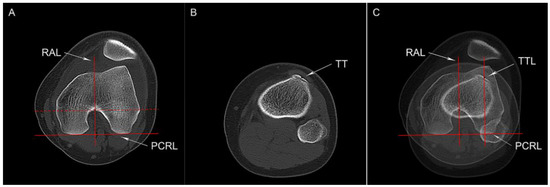

2.3.4. Knee Joint Rotation and Tibial Torsion